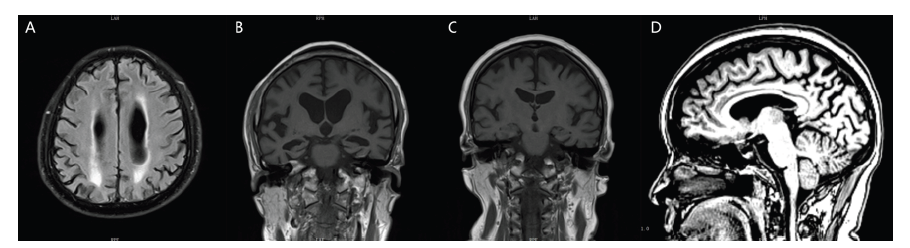

有12例患者的头颅结构影像表现为不同程度的额颞顶叶皮层萎缩,多为不对称性的,其中有8例患者出现不同程度的脑白质损害(图A)。所有患者均完成头颅MRI显影的内侧颞叶萎缩(MTA)视觉评分[5],有10例患者出现海马萎缩(图B);有4位患者的海马是正常的(图C),但均出现后扣带沟、顶枕沟增宽,后方扣带回和楔前叶萎缩的顶叶萎缩(图D);有1例患者未见明显的脑萎缩。

图A 病例8患者头颅MRI T2 FLAIR像脑白质损害融合成大的病灶;图B 病例8患者头颅MRI T1像冠状位见海马重度萎缩,MTA评分4级;图C 病例4患者头颅MRI T1像冠状位见海马正常,MTA评分0级;图D 病例4患者头颅MRI T1像失状位见后扣带沟、顶枕沟增宽,扣带回后方和楔前叶萎缩。

Fig.A T2-weighted Flair MRI images showing white matter lesions fused into large lesions in Case 8;Fig. B T1-weighted MRI images showing severe hippocampus atrophy in coronal position, and MTA score is 4 in Case 8;Fig.C T1-weighted MRI images showing normal hippocampus in coronal position, and MTA score is 0 in Case 4;Fig.D T1-weighted MRI images showing the posterior cingulate groove, parieto-occipital groove widening, cingulate back posterior and anterior cuneiform atrophy in sagittal position in Case 4.

不同的患者磁共振的表现差异较大,缺乏特异性;患者评估时的年龄越小,神经心理量表得分越高的,其磁共振的表现肉眼看有可能是正常的或者是只有轻度的顶叶萎缩。晚发型AD在结构核磁的表现主要是内侧颞叶萎缩,临床上常用的是目测法,即内侧颞叶萎缩(MTA)视觉评分:通过MRI冠状位,对萎缩的海马进行分级,从正常到严重萎缩分为0~4级[5]。MTA对鉴别晚发型AD的敏感性和特异性较高[17],但对于鉴别早发型AD缺乏特异性;早发型AD相对于晚发型AD,内侧颞叶萎缩不明显,而顶叶、外侧颞叶的改变更加突出[18]。可以对一个高度怀疑阿尔茨海默病的患者进行随访复查,观察内侧颞叶萎缩是否有进展;对于年轻的患者,需要注意有没有以后扣带沟、顶枕沟增宽为表现的顶叶萎缩。